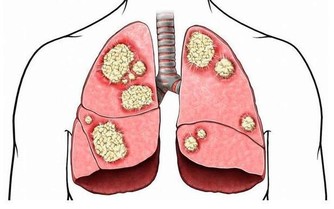

(3) 鼻竇炎超過 12 週就被稱為「慢性鼻竇炎」。

慢性鼻竇炎患者除了有上述症狀外,還會伴有咳嗽、支氣管炎和哮喘。

急性鼻竇炎可以用抗生素治療,而慢性鼻竇炎則需要手術治療。